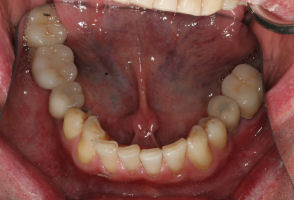

This is an advanced set of dental procedures best carried out by prosthodontists or restorative dentists. Full mouth rehabilitation is a term used in dentistry for rebuilding teeth and supporting structures after decay and gum disease has been stabilised. Full mouth rehabilitation is only required if your bite has collapsed or you have multiple missing or heavily filled teeth. Implants, crown and bridgework and/or partial or full dentures can be used to restore your bite close to its original height. Temporary restorations or dentures are used to get an idea of what the final result will be like before having the final restorations made. Temporary restorations also allow you to have input into your appearance and smile giving you the opportunity to show friends and family what your teeth may look like when the work is complete.

Before/After